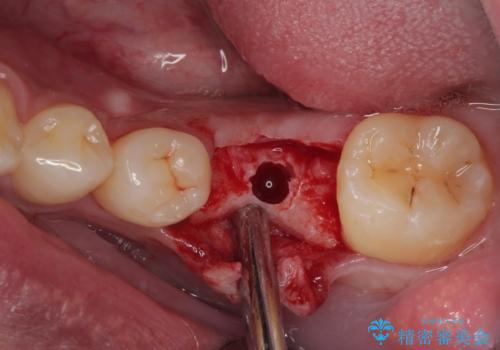

インプラント部は埋入とともに仮歯を装着し、同時に上顎奥歯の部分矯正を開始することとしました。

- 外科手術のため、術後に痛みや腫れ、違和感を伴います